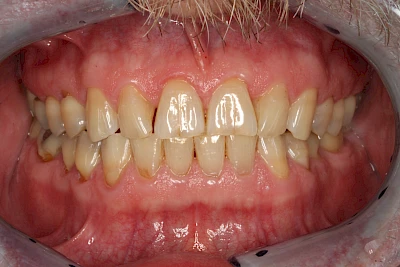

Die Zähne können dabei auf Reize (warm, kalt, süß, sauer) oder auch beim Zähneputzen empfindlich oder schmerzhaft sein. In allen diesen Fällen ist es sinnvoll, den Zahnarzt zu kontaktieren und das weitere Vorgehen abzustimmen.